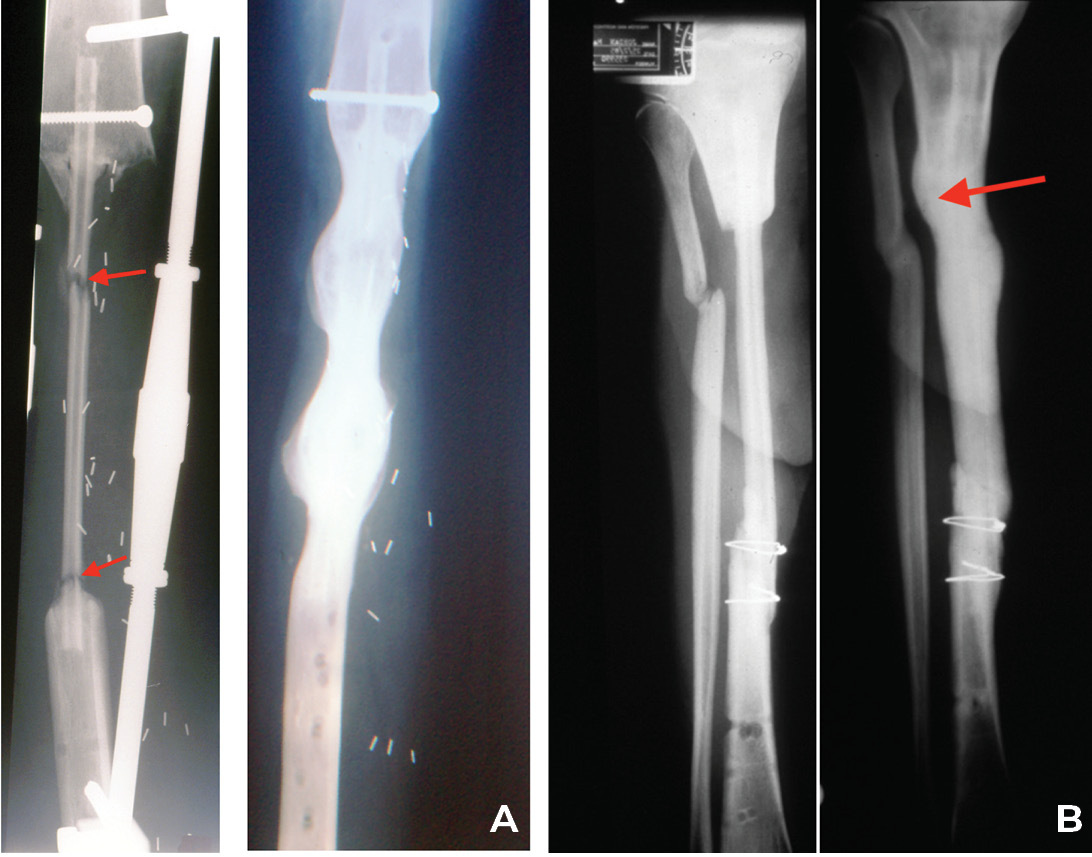

- The lower limb: This is where protected stress on the fibula in the line of weight bearing, is so important, otherwise it will not hypertrophy (see Case 14 below). This is why we always place the fibula within the medullary cavity of the recipient long bone. For the femoral shaft we choose an external fixateur. David Young, an eminent orthopaedic surgeon and a neighbour at the time, designed his fixateur for our first case. Pins are placed above and below the fibula after inserting it into the femur and sited to prevent it ‘telescoping’ within the recipient bone. Three parallel rods are attached to the pins, shown in Case 9, that can be released one at a time to allow stress on the transplant (Figure 30).

The same applies in the tibia, where the fibula is placed always within the medullary cavity of the bone. There it has been maintained again with the external fixateur or simply an above-knee plaster cast. Notably hypertrophy is frequently initiated by an undisplaced, often unidentified stress fracture as shown in Cases 1, 9, 10 and 11 (Figures 5, 30 and 31). If a specific fixateur is unavailable, in an emergency several transverse pins, a bit of bone cement and any nearby long metal rod or stick will do!

Another form of fixation is an intramedullary nail or rod used in two of our nine cases of resection of a pseudarthrosis of the tibia in a child shown in Cases 12 and 13 (Figures 32 and 33). In these two cases, the distal tibial fragment could not be fixed to the fibula with a screw. Instead a Rush nail was passed from below through the heel, calcaneum, talus and distal tibia and into the medullary cavity of the transplanted fibula. The result was exactly the same as the other seven cases. Even in plaster you can’t keep a child still! By six weeks all, including the two with nails, showed union and early bone hypertrophy (Figures 32 and 33).

The importance of centralising the fibula within the medullary cavity of the femur or tibia is again reinforced by another case done at the Royal Melbourne Hospital. The fibula was used to reconstruct the femur but fixed rigidly with a plate and screws in Case 14 (Figure 34A). Twelve months later there was union but no sign of hypertrophy of the transplant. Then the plate broke. A Kuntscher nail was inserted from above and down through the medullary cavity of the fibula. It shattered forming a row of ‘bangles’ around the nail (Figure 34B). Two years later, having walked on his ‘box of bones skewered by the K-nail,’ he was located and the leg radiographed. Except for one level, there was union and hypertrophy of all bone bangles (Figure 34C).